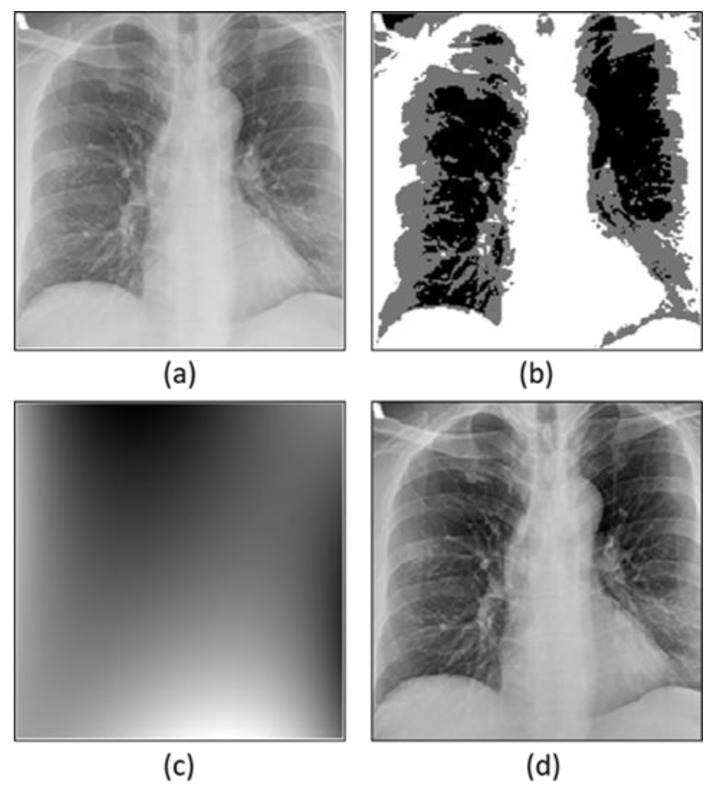

3.2.1. Bias Field Correction

Bias field correction is an approach used to enhance the quality of an image [54]. Mostly there are intensity in-homogeneity issues in the images because of the bias field signals. These bias field signals are the signals with low frequency, and they are responsible for bringing down the high-frequency information thus reducing the quality of images. Therefore, bias field correction is used to address this problem which is based on energy minimization operation. The bias field correction is applied in two steps by decomposing the images into two multiplicative components. First, the estimation of the bias field is performed and second, bias field correction is conducted (Figure 2). The energy minimization strategy [55,56] is used to optimize these two components.

Figure 2.

Application of bias field correction of the X-ray image. (a) Original image, (b) segmentation of inhomogeneous intensity, (c) estimated bias field image, (d) bias field correction image.